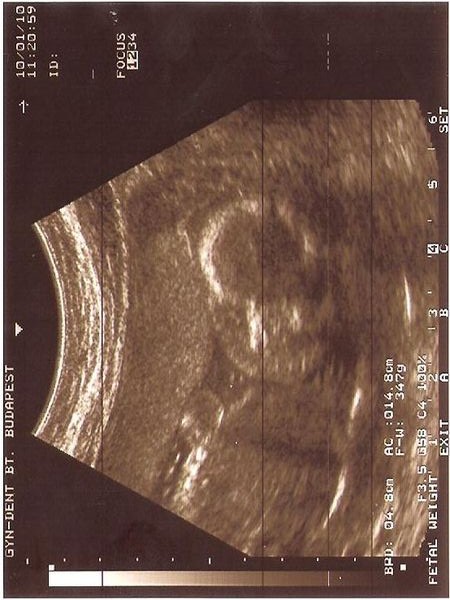

Kép

Flóra/Zoé Baba érkezik

doki: ápr.12.

4D UH: ápr. 30. - uhhhh, de soká